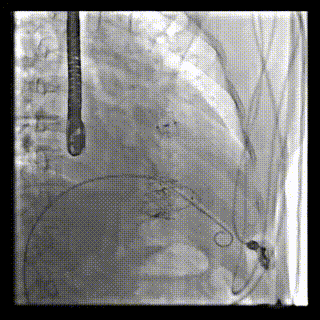

本周三例接受LuX-Valve Plus經血管三尖瓣置換術的患者中,第一例患者為冠狀動脈旁路移植術+Bentall+二尖瓣成形術后;第二例患者為永久起搏器植入術后,存在跨三尖瓣導線;第三例患者合并房顫、房缺及左心耳封堵術后。

三例患者入院后,葛均波院士團隊周達新教授、潘文志教授、張源博士、陳莎莎博士及心超室的潘翠珍教授、李偉教授對患者的情況進行詳細評估和討論,最終決定為三例患者選擇LuX-Valve Plus40mm、50mm和50mm型號的瓣膜進行手術治療。手術后即刻拔除氣管插管,術后患者三尖瓣反流癥狀得到顯著改善,復查心超結果顯示人工三尖瓣瓣膜支架固定穩定,瓣葉關閉形態未見異常,未見明顯反流。